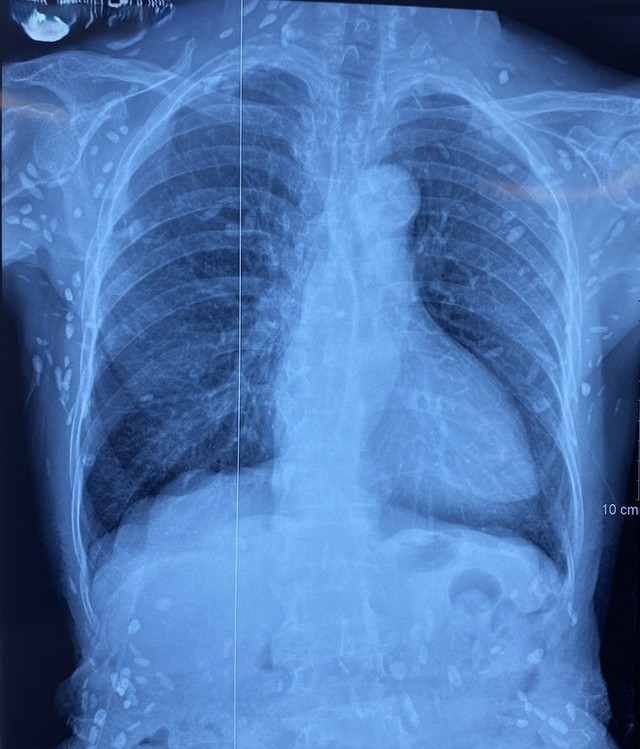

Người bệnh được chuyển lên từ tuyến trước vì rối loạn ý thức đe dọa suy hô hấp, hình ảnh cắt lớp vi tính sọ não và X-quang ngực cho thấy rất nhiều nốt cản quang trong nhu mô não và dưới da vùng ngực-bụng.

Nhiều nốt cản quang dưới da thành ngực-bụng và chi trên. Ảnh: Bệnh viện TWQĐ 108

Mặc dù xét nghiệm kháng thể IgM với sán dây lợn âm tính, các tổn thương trên X-quang gợi ý người bệnh trước đây bị nhiễm ấu trùng sán dây lợn, sau đó các nang sán trở nên vôi hóa và tồn tại lâu dài trong tổ chức. Người bệnh được điều trị theo phác đồ bệnh chính, đáp ứng và ra viện tiếp tục điều trị theo tuyến.

Nang sán dây lợn có thể tự thoái hóa hoặc bị vôi hóa, tạo nên nhiều hình ảnh cản quang phát hiện được trên phim X-quang như trường hợp bệnh nhân trên.